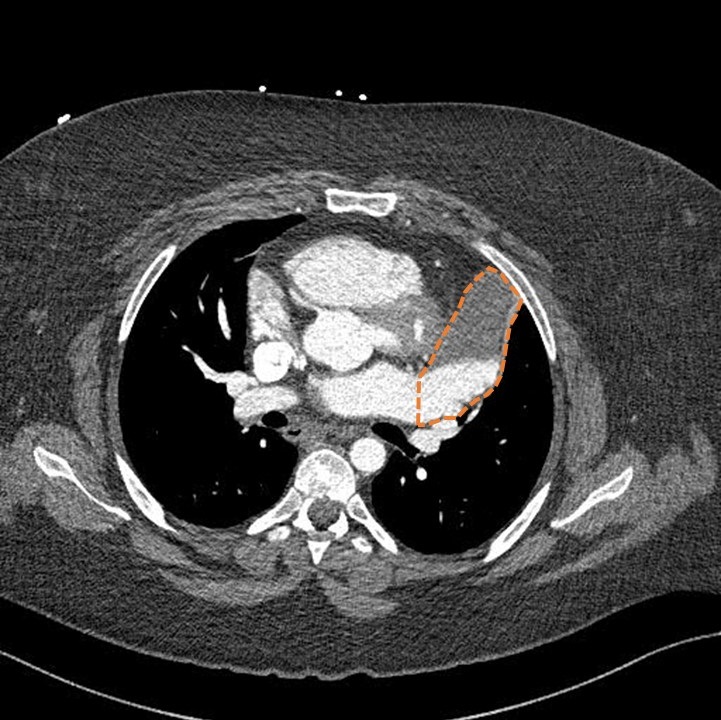

Very interesting data! Keep a eye out for editorial with @akillumd discussing this innovative paper. An opportunity to improve safety. @shivkumarmd

What are the barriers to doing this in all labs, if ZERO RV punctures? Would love to hear your thoughts👇 New Era in Epicardial Access for the Ablation of Ventricular Arrhythmias: The Epi-Co2 Registry https://t.co/kWqnord2wR